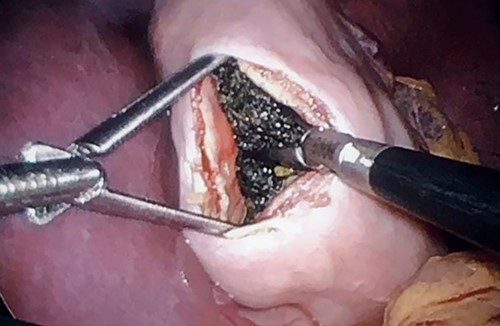

Therefore, the family was consulted about removing the bezoar surgically. The procedure was performed laparoscopically with three working ports: two working 5-mm ports and one 11-mm camera port. A 5-cm gastrostomy at the body of the stomach was done (Fig. 2). A large bezoar was found at the pylorus, extending to the duodenum. The large bezoar was removed with an endo grasper, and the stomach was closed with a Vicryl suture. An Endo-leak test was performed, and the specimen was removed from the umbilical port with an endo bag. The bezoar was extracted with no spillage in the abdominal cavity, and none remained in the stomach (Fig. 3).

There are three techniques are described in the literature. First, Don et al. described passing a 10-mm port into the gastric wall to create an intra-gastric port, followed by removing the specimen with a gastroscope [13]. Second, Kanetala et al. described a similar approach using two gastric ports to cut the bezoar into small fragments and removing them via gastroscopy; both approaches are time-consuming [13, 14]. The third technique, described by Shami et al. [15], was used in our case. In our case, we performed a gastrotomy, extracting the specimen with a grasper and placing it in a Endo-bag then removing it through the 10-mm camera port. We did not experience any spillage or post-operative infection. A laparoscopic approach is also an option; however, it can be time-consuming and technically challenging cases. There is as of yet no gold standard procedure due to the rarity of the disease; however, it should be performed with attention to patient safety and outcomes.